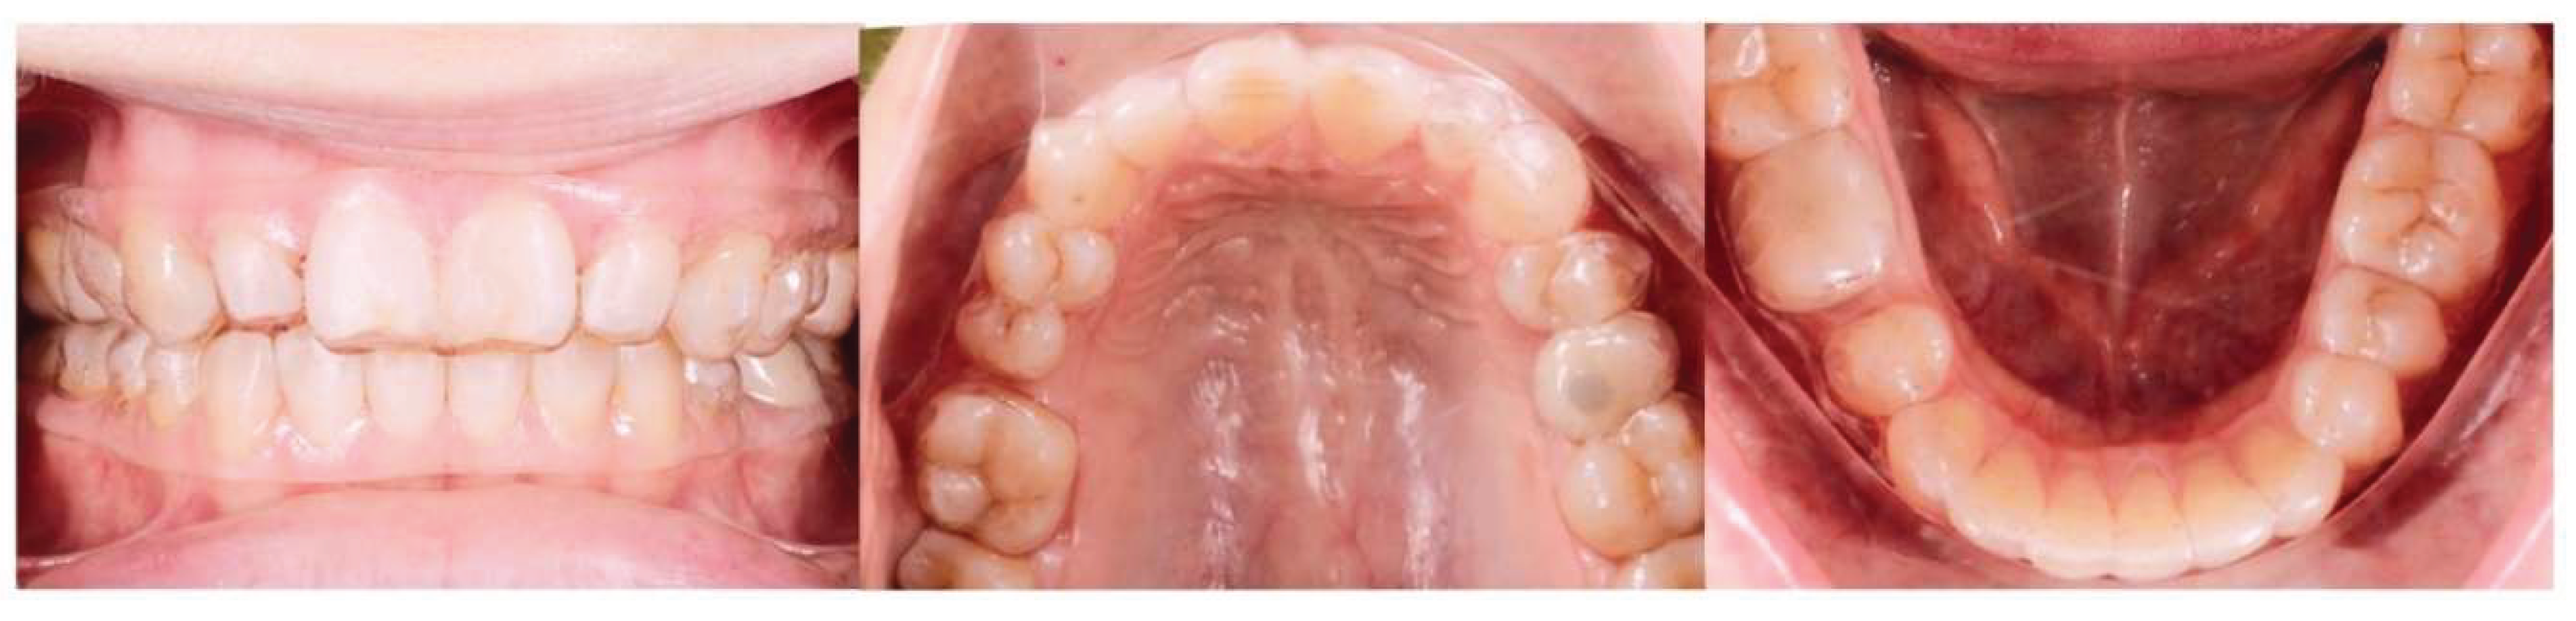

Background: While mini-screw-assisted rapid palatal expansion (MARPE) is effective for correcting maxillary transverse deficiency in adults, perimaxillary suture disarticulation—particularly at the pterygomaxillary junction—can be inconsistent. This study evaluates skeletal and dentoalveolar outcomes of a novel 3D-guided midpalatal piezocorticotomy-assisted MARPE protocol, focusing on expansion symmetry and pre-existing asymmetries. Methods: Three adult patients were retrospectively analyzed after treatment with 3D-guided midpalatal piezocorticotomy-assisted MARPE expansion and one with non-guided midpapalatal piezocorticotomy and MARPE expansion. Surgical guides were digitally designed using CBCT data to align with the nasal septum orientation in multiple planes. Perimaxillary suture disarticulation was measured pre- and post-expansion, and dentoalveolar changes were evaluated. Post-expansion asymmetries were addressed using directly printed aligners. Results: Complete midpalatal suture separation (mean 8.48 mm), involving both anterior and posterior nasal spine regions, was achieved in one patient. Bilateral pterygomaxillary disarticulation averaged 1.06–1.23 mm, resulting in forward–outward rotation of the nasomaxillary complex. Additional separation occurred at the frontonasal (2.03 mm) and vomeromaxillary (1–2 mm) sutures, with no significant changes in orbital or peri-orbital sutures. One patient presented with pre-existing dentoalveolar asymmetry, which intensified the perceived post-expansion imbalance but was successfully corrected with directly printed aligners. In the second case, 5.6 mm of suture separation resulted in a limited lateral nasal width increase (<1.5 mm), while maxillary base expansion exceeded 6 mm. A significant canine plane cant (1.2 mm) and divergent axial inclinations of the maxillary central incisors relative to the palatal plane were also observed. In the second case, a non-impactful palatal bone fracture with asymmetric displacement of the left palatine fragment was documented. After 16 months of aligner therapy, all cases exhibited favorable remodeling of the palatal structures, midpalatal suture, and alveolar processes, accompanied by improved dental alignment, occlusal plane symmetry, and mandibular dentoalveolar adaptation. The dento-alveolar expansion achieved in the third case over the course of 16 months of treatment was approximated at 4 mm. The fourth case showed consistent improvement with direct printed aligners after MARPE midpalatal diasrticulation of 11 mm after experiencing minor bone fracture. Conclusions: Human skulls exhibit considerable variability between the left and right sides, which can influence spatial balance. Pre-existing cranial asymmetries appear to be the primary contributors to asymmetry following MARPE treatment. Careful evaluation of dentoalveolar discrepancies and axial tooth inclinations is essential for preventing and managing potential asymmetric dental arch outcomes during the post-expansion phase. Although peri-maxillary bone fractures are relatively uncommon, their occurrence is influenced by multiple factors. Adjunctive techniques, such as 3D-guided midpalatal piezocorticotomy, show promise in significantly lowering the risk of intra-expansion peri-maxillary fractures.